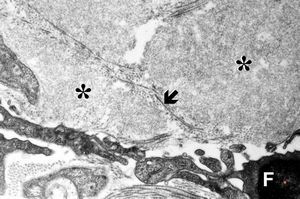

F,45y. | jejunum … amyloidosis